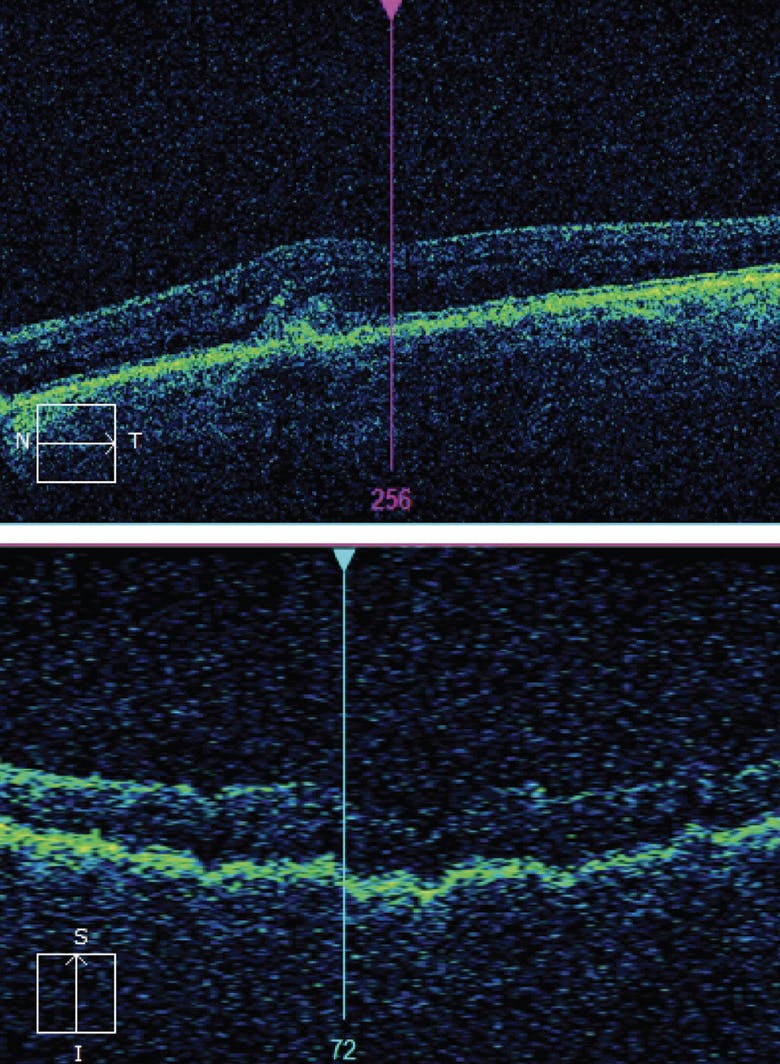

In January 2022, my office was alerted to aberrations in her at-home testing of the left eye. The patient presented the next day, explaining that her vision had not subjectively changed since last month’s visit. Dilated fundus examination did not show significant new abnormalities, but in-office OCT revealed a new, small CNV with very subtle subretinal fluid (Figure 7). Vision had dropped to 20/30 OS. She was diagnosed with conversion to wet AMD with active CNV in the left eye and received an intravitreal injection of an anti-VEGF agent.

<p>Figure 7. Six months after the right eye converted to wet AMD, at-home monitoring caught changes in the left eye (A), prompting in-office examination and a new diagnosis of wet AMD in the left eye (B).</p>

Figure 7. Six months after the right eye converted to wet AMD, at-home monitoring caught changes in the left eye (A), prompting in-office examination and a new diagnosis of wet AMD in the left eye (B).

At her last follow-up in February 2022, the patient’s VA was stable at 20/20 OD and 20/25 OS, and her OCT imaging shows signs of improvement (Figure 8). She is now scheduled for anti-VEGF injections every 4 weeks.

<p>Figure 8. At her last follow-up the patient was stable with improvement seen on OCT imaging in the right (A) and left (B) eyes.</p>

Figure 8. At her last follow-up the patient was stable with improvement seen on OCT imaging in the right (A) and left (B) eyes.